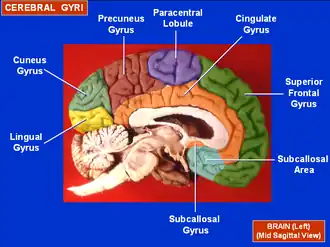

Medial view of a halved human brain (Paracentral lobule labeled at top center, in blue.) | |

Medial view of a human right cerebral hemisphere. Paracentral lobule is labeled at top center, in blue.

Medial view of a human right cerebral hemisphere. Paracentral lobule is labeled at top center, in blue. -